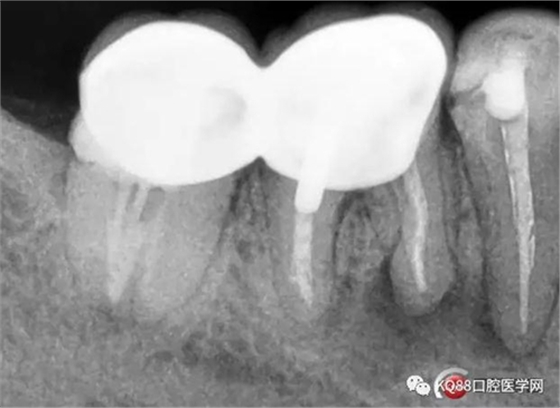

46/47金瓷烤瓷聯(lián)冠修復(fù)后

(本病例系采用歐羅得卡大錐度根管銼機(jī)擴(kuò))